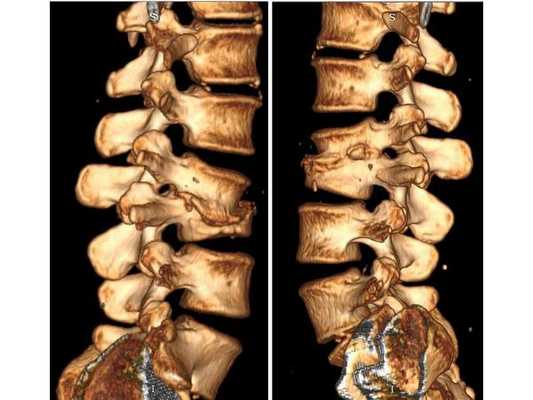

КТ пояснично-крестцового отдела позвоночника показала состояние после перенесённого спондилодисцита L2-L3 (воспалительного заболевания инфекционного характера) с разрушением тела L3 позвонка и кифотической деформацией (искривлением позвоночника) на данном уровне.

Состояние после перенесённого спондилодисцита L2, L3 позвонков с формированием абсолютного стеноза (критического сужения просвета в позвоночном столбе) на уровне L2-L3 и развитием нижнего парапареза